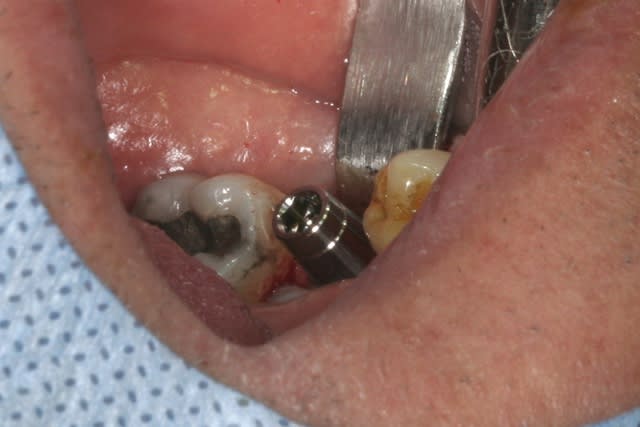

l'interactive, (t'ain qu'il est beau!!!)

mise en place au CA qui bloque à 45Ncm...on est à 1 ou 2 mm de la crête....pas de problème, on retire le Fm (sympa, la vis, car il y a un filetage dans le Fm, ne risque plus de tomber!!!) et on se reprend direct dans le col de l'implant à la clef à cliquet...comme d'hab quoi...;-)

mise en place de la vis de cicat basse pour augmenter l'épaisseur de gencive attachée et on suture par dessus...si çà s'operculise, c'est pas grave en plus

@ fouilla: la vis de cicat n'est pas crestale, la pano est trompeuse, cette surélévation de 2mm va permettre d'augmenter la hauteur de tissu conjonctif dans cette zone.

il sera plus facile de "tricher" ensuite pour rendre l'émergence prothétique la plus anatomique possible...

un petit exemple: il est conçu pour pouvoir être posé légèrement supra crestal, de par le biseau de col qui fait 0.25mm de haut quelque soit le diamètre de l'implant, mais en plus, entre la première microgroove et le haut du biseau on à près d'1mm qui peut être exposé sans incidence pour la suite...

ne me dites pas que vous avez tout le temps des crêtes plates comme des plateaux de billard (là c'était quasi le cas...) ou sans un petit défaut vestibulaire!!! cette caractéristique permet donc beaucoup plus de souplesse dans le positionnement 3D de l'implant